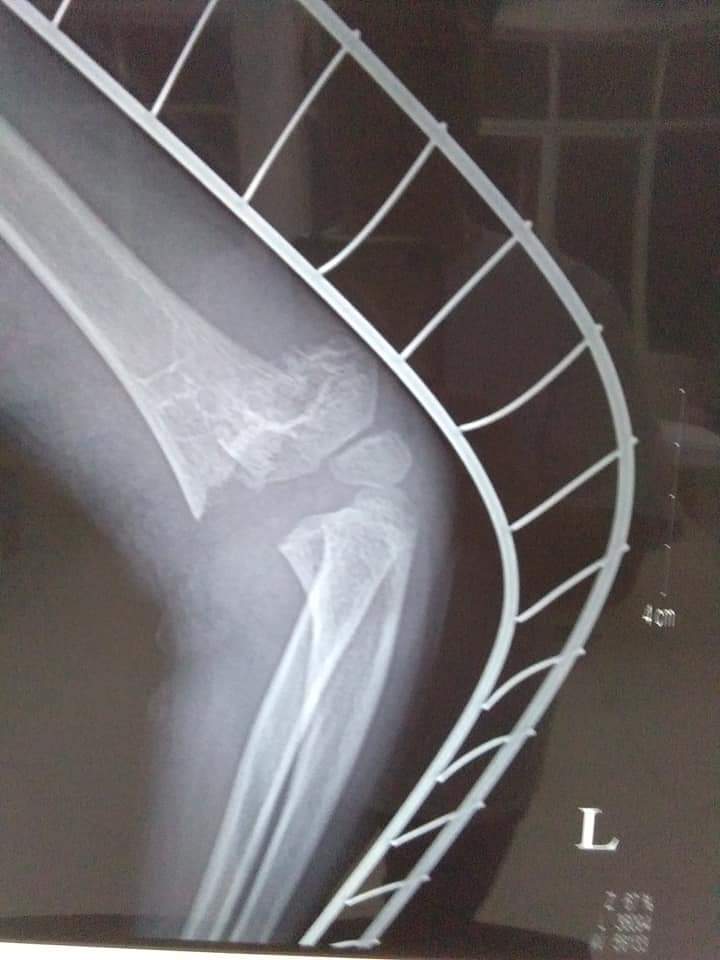

Những hình ảnh trước và sau bó bột tại Trung tâm y tế huyện Nghi Xuân

Hình ảnh trước nắn

Hình ảnh sau nắn